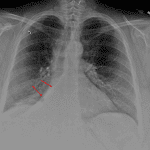

Age: 55

Sex: Female

Indication: Hemoptysis

Sample ReportRight middle and lower lobe collapse. Recommend chest CT to assess for a central obstructing mass.

No pleural effusion.